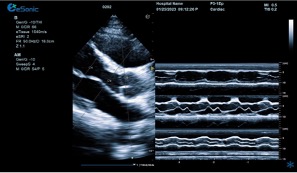

相关心脏应用功能--M型、解剖M型

18dd0675d53918b7d05ea7a823af71a.png

M型-最常用的心功能检测法;高血压病除二维观察外,其室壁增厚及心腔大小的改变,均也可通过M型测量而获得

解剖M型-适用于心尖上翘者、瘦长体形者、室壁瘤形成等...

相关心脏应用功能--M型、解剖M型技术总结:

1edf4ffc259114ab6502340e160add1.pngM型超声是评估心脏功能的重要方法之一,通过其高速的取样帧频,可以将心脏各个阶段的运动状态显示出来。

解剖m型:

不受角度限制,打破技术壁垒不影响M型图谱分辨率。

三线解剖M型:

同一心动周期,多节段评估心功能。

解决节段运动异常和判断同步化运动。

彩色M型:

直观显示室璧运动和血流动力学关系。

更精准判断血流时向,更精准评估心脏功能。